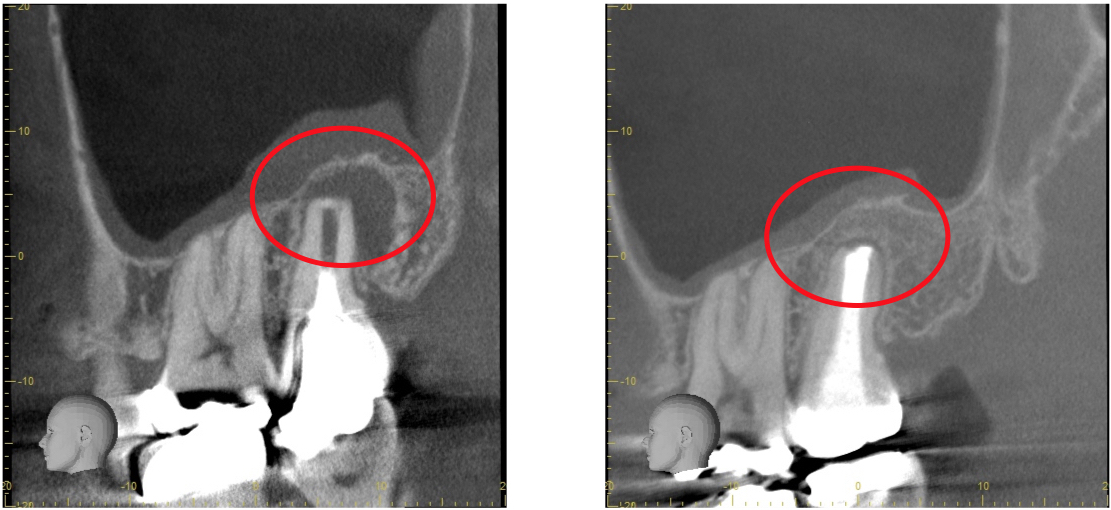

歯科用CTとは一般の医療用CTを歯科治療用に特化した装置です。

当院ではこの歯科用CTを使用して三次元で歯の構造を把握します。

任意の角度や位置から歯・顎骨を確認することもできるので治療の精度が大幅に向上します。